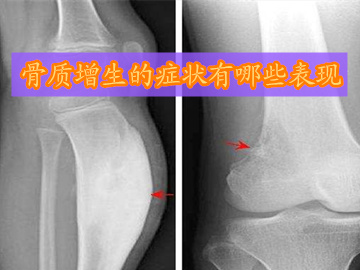

1、膝关节骨质增生的症状:起初疼痛多发生在长时间行走或上下楼梯时,但休息或起床后会有所好转。可随着病情的发展,走平路也会感到疼痛,膝关节活动也会受到限制,同时膝关节活动时有像捻头发时所发出的响声。